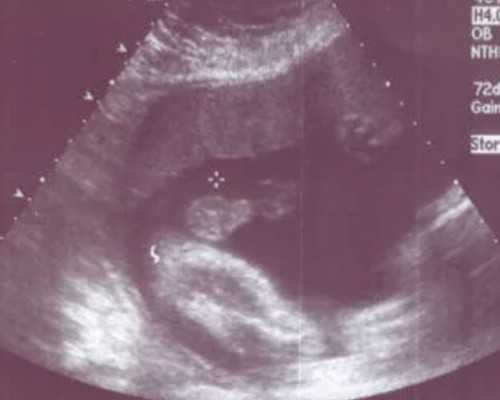

4、先兆流产:如果移植后小肚子抽搐同时伴有肚子疼痛、阴道出血等情况,可能是先兆流产。可遵医嘱使用黄体酮胶囊、地屈孕酮片等药物进行保胎治疗。如果胚胎发育异常,可能需要进行清宫手术终止妊娠。